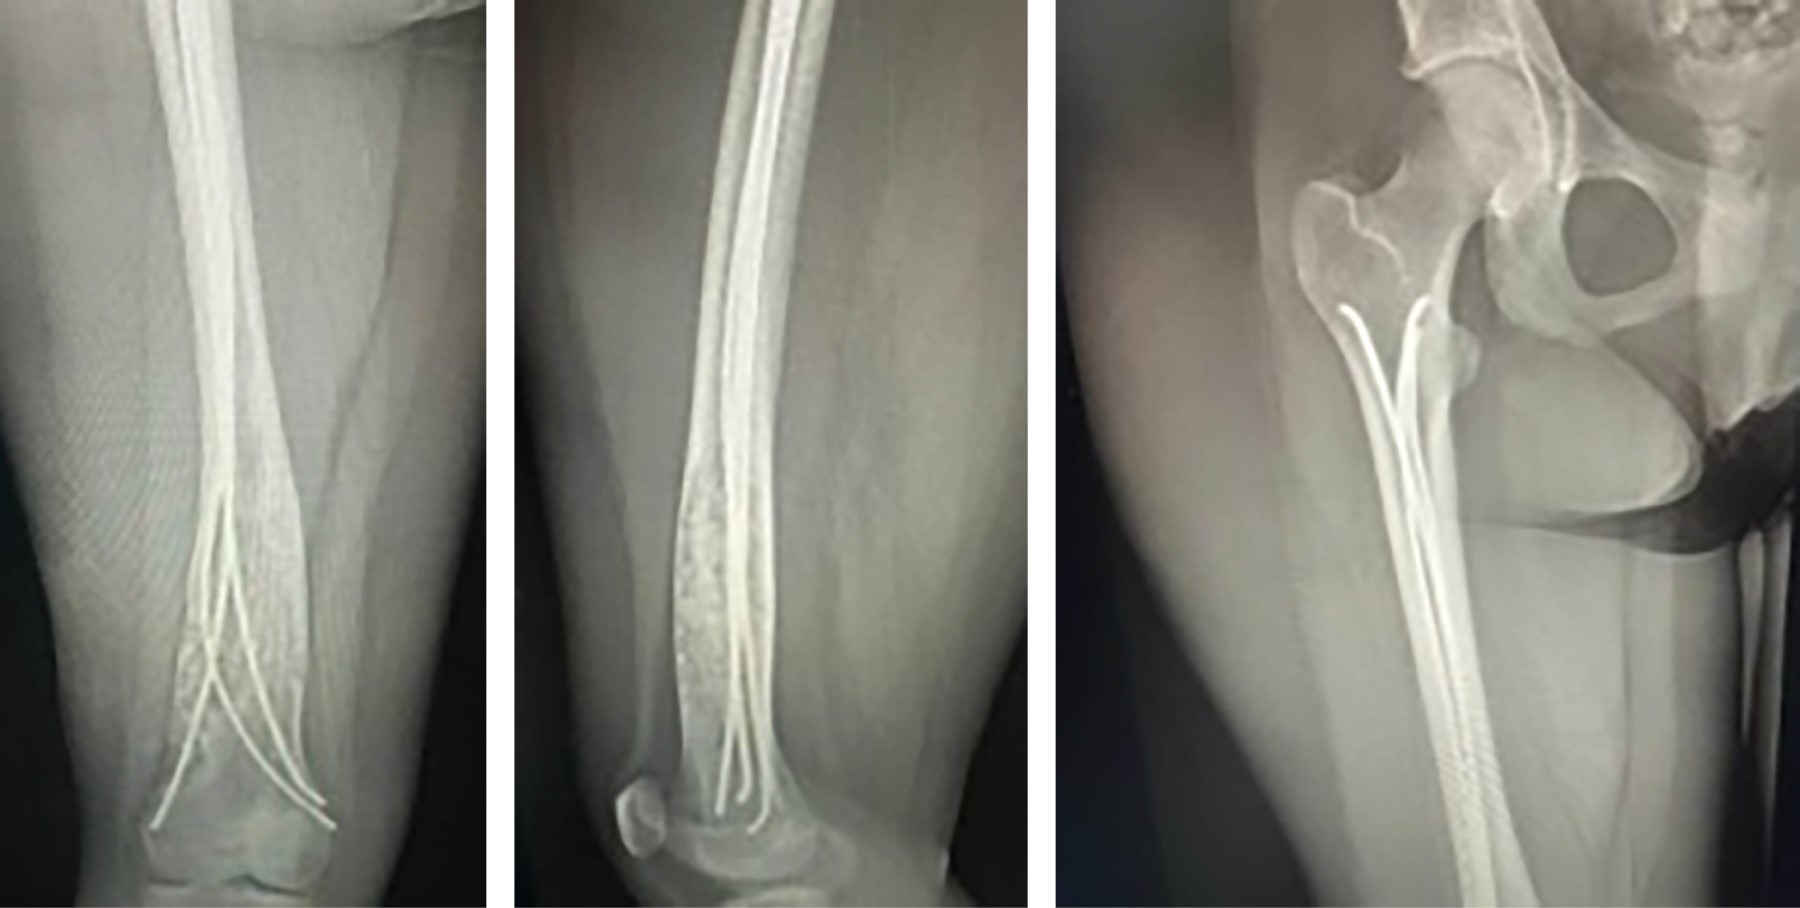

Paciente adolescente femenina de 12 años es evaluada en compañía de su madre, derivada por gonalgia izquierda en estudio de un año de evolución y tumor de fémur distal y tibia proximal izquierda, que se evidencia en radiografía anteroposterior (AP) y lateral de rodilla izquierda (Figura 1) y en radiografía AP y lateral de fémur distal izquierdo (Figura 2). Al examen físico presenta claudicación a la marcha y rango de movilidad de rodilla izquierda disminuido con dolor a la flexión > 90°. Se realizó resonancia magnética nuclear con contraste (Figura 3) con el hallazgo de una lesión hipercaptante, hipointensa en T1, hiperintensa en T2, además de lesión cortical a nivel de ambos fémures distales. Se complementa estudios con exámenes endocrinos con resultados dentro de límites normales y radiografías de huesos largos descartando algún otro foco de lesión.

Figura 3